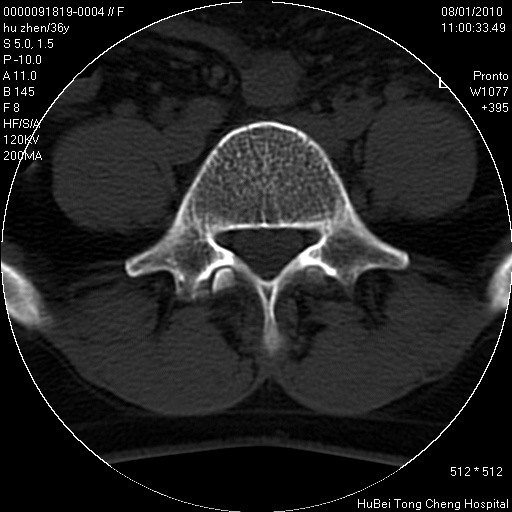

患者 女,36岁。右侧腰腿痛半月余。腰骶椎mr平扫偶然发现骶椎异常信号。

临床诊断:1)腰椎间盘突出症。2)骶椎肿瘤性病变?

骶椎ct平扫(层厚、层距均为5mm),图像如下:

考虑s1骨纤维异常增殖症。

良性骨病变,骨纤还是骨母细胞瘤?